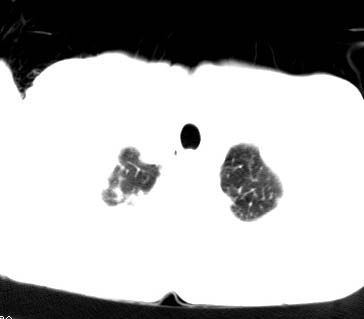

结核是要考虑,但肺癌也不能排除.

右上肺结核,请结合痰检除外活动期;右上叶支气管官腔狭窄建议支气管镜或抗僗后随诊除外堵塞性改变。

高度怀疑肺癌,强烈要求纤支镜检查。

支持双上肺继发性肺结核。